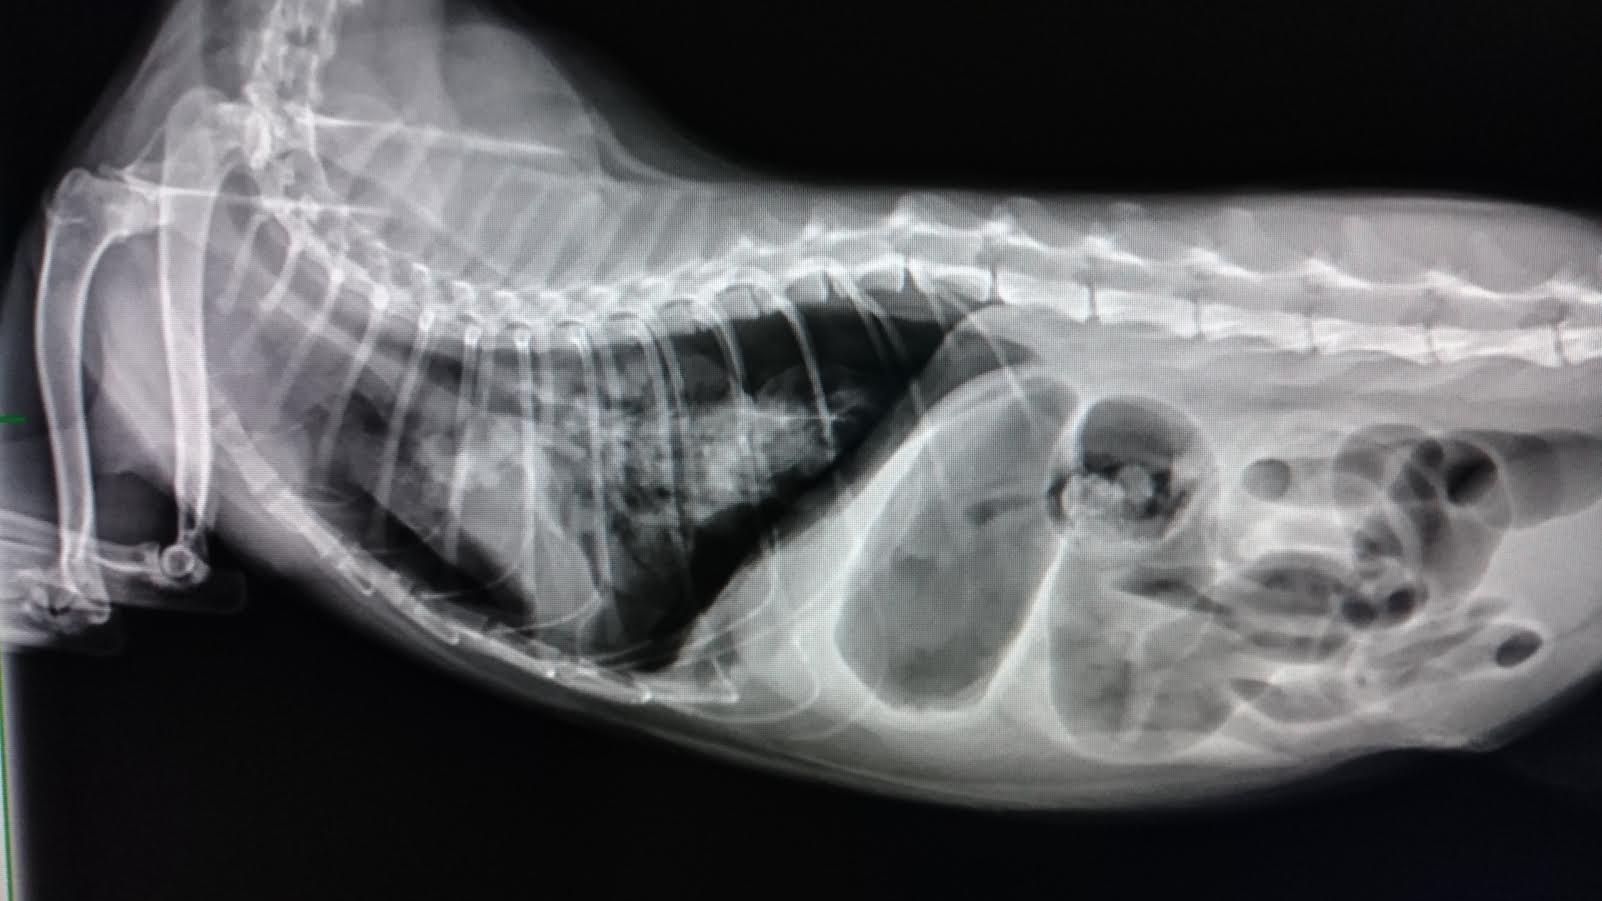

Eve 今日照X光,心臟前後仍有些團塊霧點

(過去Eve因氣胸而肺部被壓縮到非常小,後來把空氣抽掉後,肺部有慢慢擴張,X光下很花很霧,而後逐漸有變乾淨,但團塊感一直消不掉)

因此仍無法完全排除腫瘤或黴菌或是寄生蟲的感染,

期間院方除了氣管灌洗外,也為為EVE拍攝X光觀察肺部團塊,